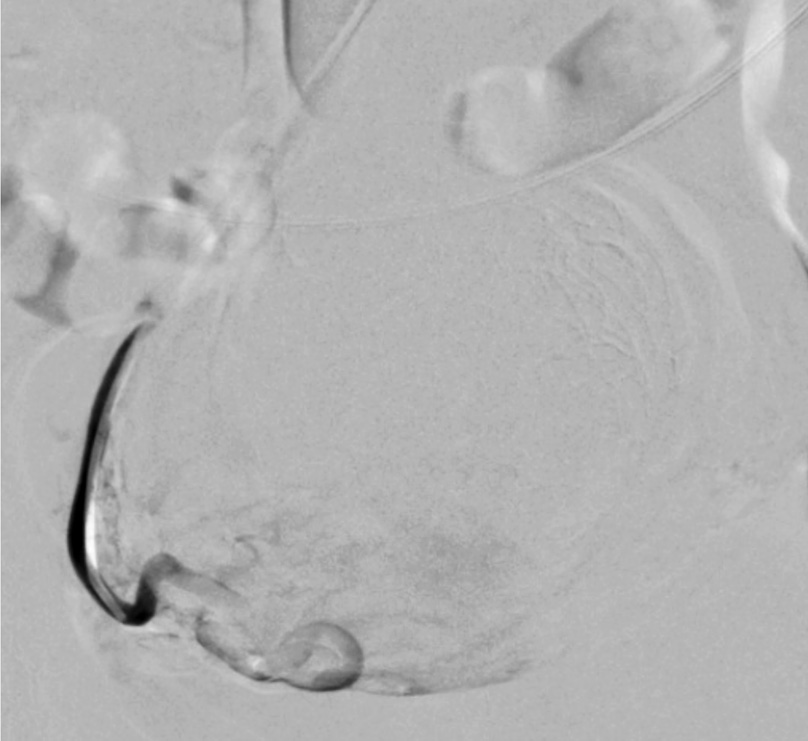

Выполнены пункция и катетеризация правой лучевой артерии в ретроградном направлении. Далее катетером выполнена селективная катетеризация правой и левой маточных артерий. Выявлена миома матки больших размеров с выраженным перифиброидным сплетением. При проведении ангиографии брюшной аорты и таза дополнительных источников кровоснабжения не выявлено. Катетер по проводнику проведен последовательно в горизонтальные сегменты левой и правой маточных артерий, питающих узлы (рис. 8, 9). Проведена эмболизация насыщенными гадотеридолом микросферами до стаза контраста в дистальных сегментах маточных артерий. Рентгеновский контроль эффективности эмболизации – рис. 10, 11. Катетер и интродьюсер удалены. Наложена давящая асептическая повязка.

Рис. 10. Клинический пример №2. Ангиограмма правой маточной артерии после ЭМА. / Fig. 10. Clinical case 2. Angiogram of the right uterine artery after UAE.

Рис. 11. Клинический пример №2. Ангиограмма левой маточной артерии после ЭМА. / Fig. 11. Clinical case 2. Angiogram of the left uterine artery after UAE.